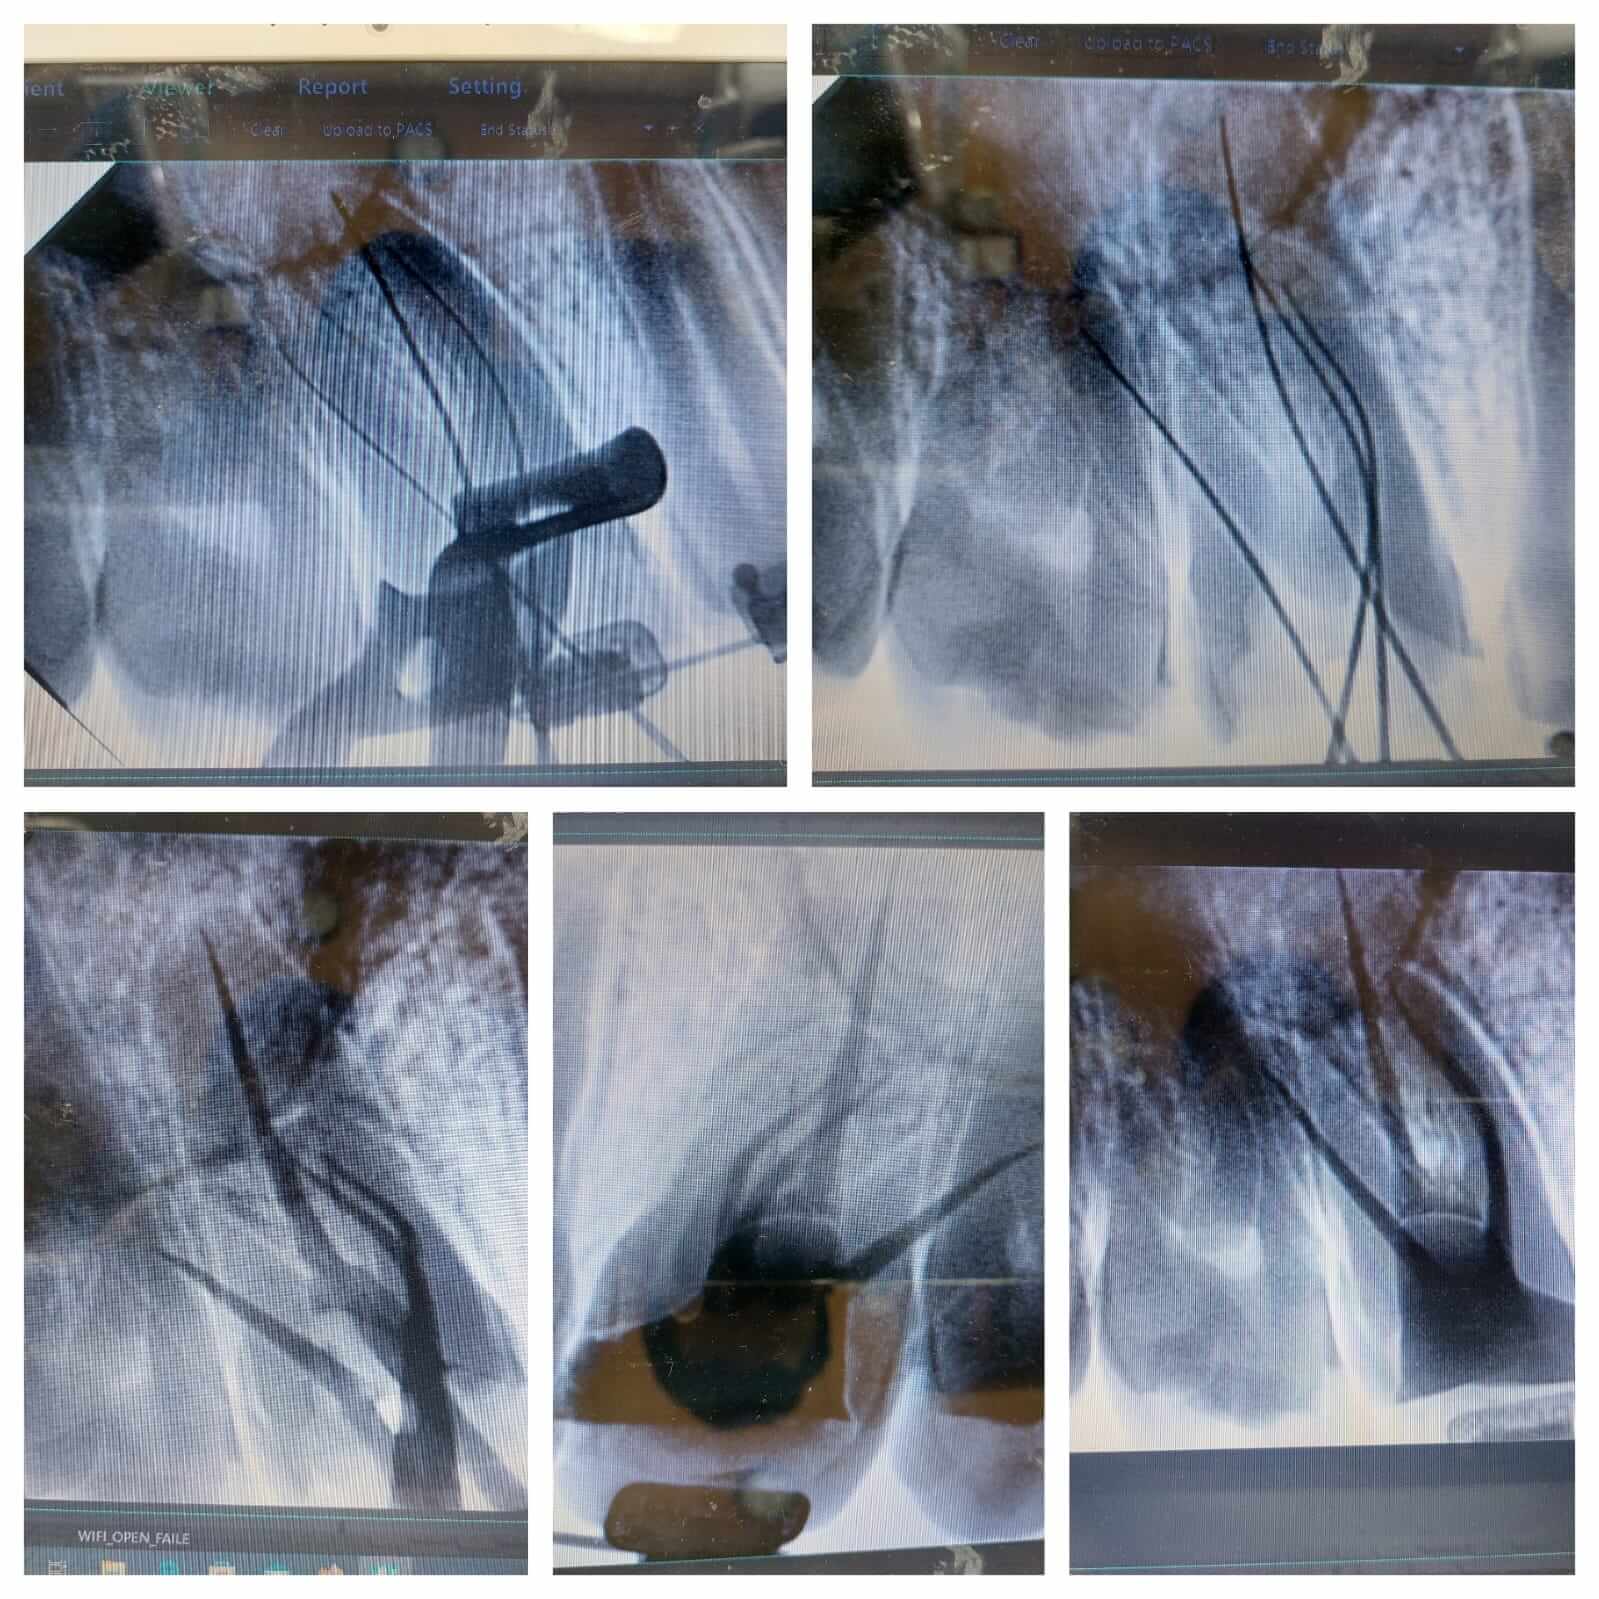

Precise root canal treatment: Working lengths measured accurately, including the important MB2 canal.